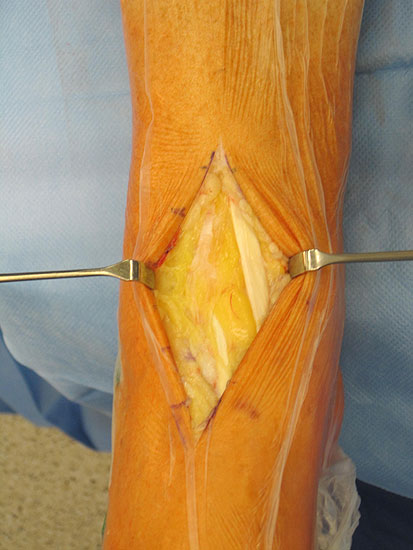

1. Wundheilungsstörung infolge einer hohen intraoperativen Druck- und Zugbelastung auf den periartikulären Weichteile; Lösung: dosierte Weichteilbehandlung durch die Hacken durch den Assistenten; aktive Erinnerungen während der Operation (Abb. 20 und 21)